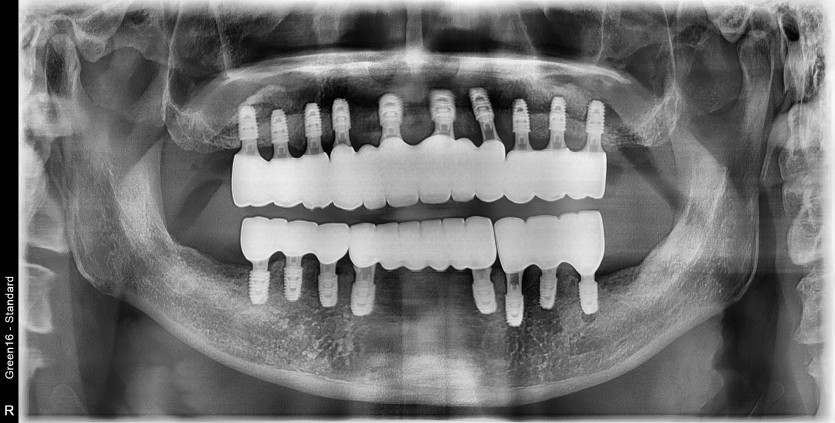

전체 임플란트 증례입니다.

18개의 임플란트로 완성하였습니다.